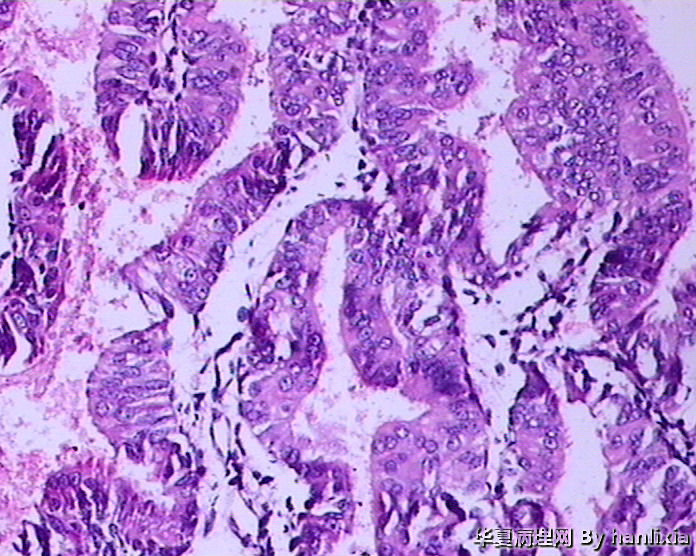

子宫内膜

标签:45岁女性 闭经1年 阴道出血10余天 行诊刮术。

支持复杂性增生伴不典型增生,细胞核淡染、核变圆,并见明显的核仁,有细胞学的不典型性

患者45岁,闭经1年,阴道出血10余天,行诊刮术,未服用止血类药物。

复杂性伴非典型增生

腺体密集,背靠背及共壁现象,腺体有成角,腺上皮增生呈多层,有内折,腺体与间质比例大于1:1.

子宫内膜复杂性增生伴中-重度不典型增生,图1-2可疑癌变